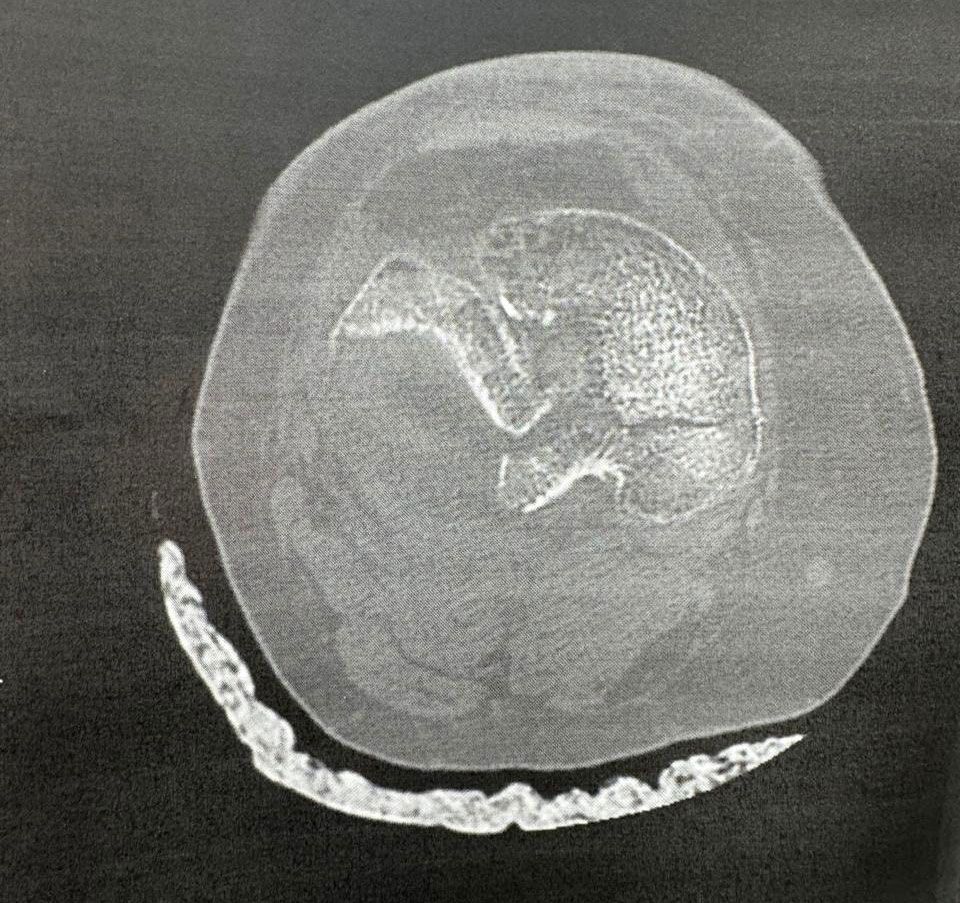

Σοβαρό ενδαρθρικό κάταγμα κνημιαίου πλατώ (Schatzker VI) — υψηλών απαιτήσεων αποκατάσταση με στόχο ανατομική ανάταξη και λειτουργικότητα γόνατος.

Αντιμετωπίσαμε ένα από τα πιο απαιτητικά και σύνθετα τραύματα στην ορθοπαιδική: σοβαρό ενδαρθρικό κάταγμα κνημιαίου πλατώ, Schatzker VI.

Μια επέμβαση υψηλών απαιτήσεων, που απαιτεί ακρίβεια, στρατηγική και απόλυτη προσήλωση στη λεπτομέρεια, με στόχο την ανατομική αποκατάσταση της αρθρικής επιφάνειας και τη διατήρηση της λειτουργικότητας του γόνατος.

Κάταγμα κνημιαίου plateau τύπου VI κατά Schatzker classification

Το κάταγμα τύπου VI κατά Schatzker είναι το πιο βαρύ είδος κατάγματος του κνημιαίου plateau. Χαρακτηρίζεται από:

- Διπλοκονδύλιο κάταγμα (έσω + έξω plateau)

- Αποσύνδεση μεταφύσεως–διάφυσης (metaphyseal–diaphyseal dissociation)

- Συχνά συνοδό σοβαρή βλάβη μαλακών μορίων

- CT scan (απαραίτητο για σχεδιασμό)